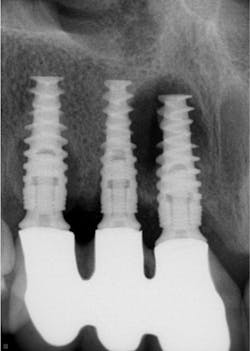

Historically, with a few exceptions, crowns did not come off in service. Zinc phosphate and conventional GI cements are rigid and strong and held the crowns on the tooth preparations. Resin cements are flexible and strong (figure 3). But one of the major reasons almost every dentist has had zirconia crowns coming off is the flexibility of resin cements and, to a lesser degree, the flexibility of the RMGI cements (figure 4).

Dental root-form titanium alloy implants were originally thought to replace teeth ideally, and even potentially to be better than teeth. Decades later, we know that is not true. Peri-implantitis, occlusal challenges, and numerous other issues have shown us that our main mission is still preservation and retention of natural teeth and that implants are a great “last resort” when teeth cannot be restored and retained (figure 4).

In-depth research needs to be accomplished on what materials would be best for dental implants and what restorative materials should be placed over implants to simulate the wear of natural teeth.